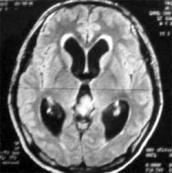

正常顱壓腦積水癥狀

• 正常顱壓腦積水

628健康網(wǎng)為您分享有關(guān)正常顱壓腦積水的癥狀,正常顱壓腦積水的治療方法,正常顱壓腦積水的預(yù)防知識(shí),正常顱壓腦積水的癥狀...